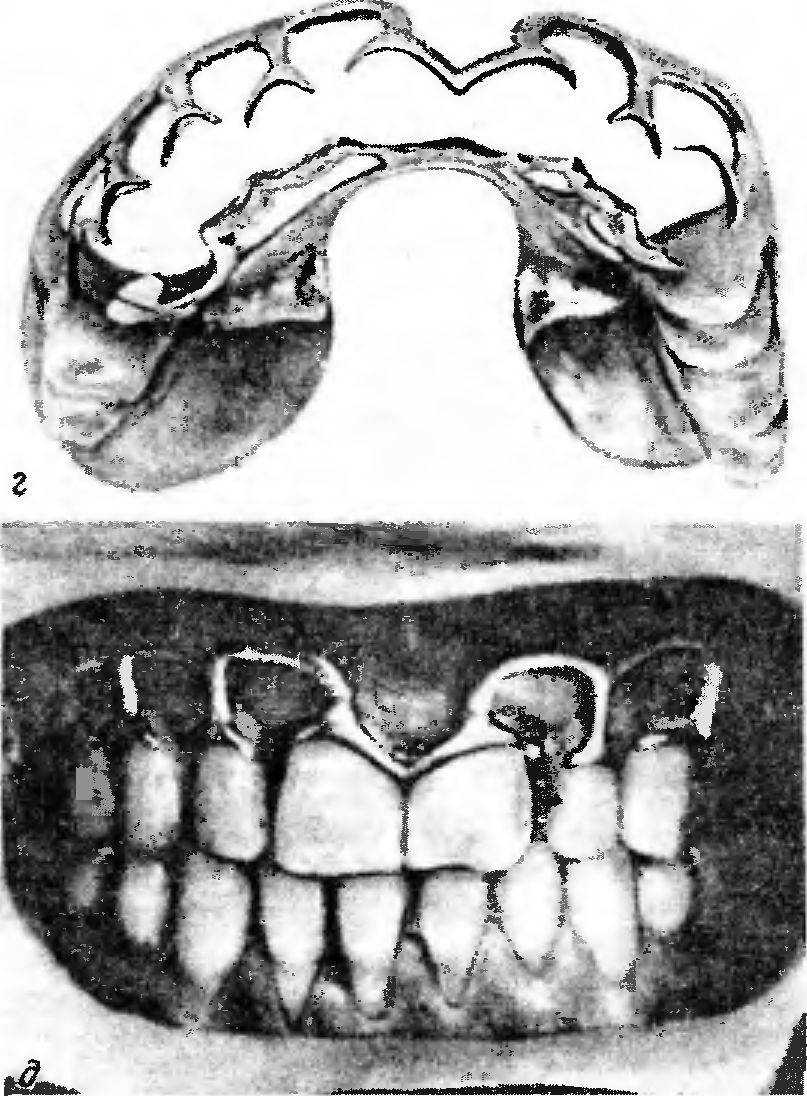

Рис. 166. Варианты сочетанных несъемных и съемных конструкций шинирующих аппаратов.

б — цельнолитая шина с системой коронок и штангой Румпеля (на группу передних зубов облицовка не нанесена — видны ретеиционные шарики); « — конструкция съемной части шинирующей системы; г, д — рессорные ответвления съемных шинирующих протезов для уменьшения давления на пародонт оставшихся зубов.

Дальнейшая работа проводится по описанной ранее методике. Для ориентировки приводим несколько разновидностей шинирующих съемных цельнолитых лечебных аппаратов и шин-протезов (рис. 165—167; рис. 166, а см. на цвет. вкл.).